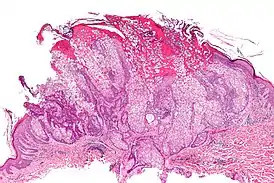

![]() Аденома сальных желёз (гистологический препарат, окраска гематоксилином и эозином) | |